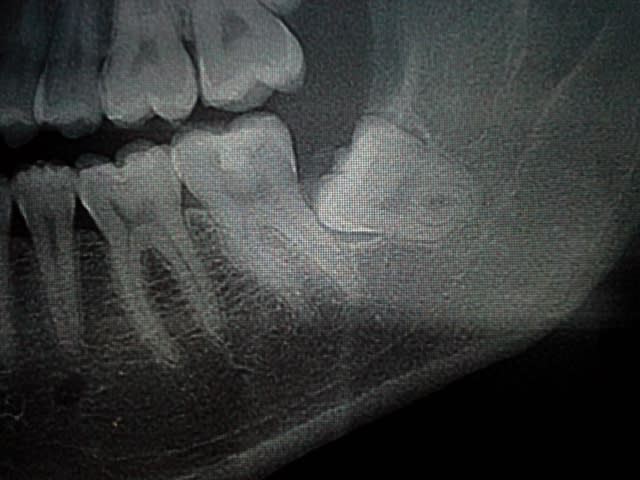

- Pouvez-vous me dire ce qu'est cette radio opacité au niveau de la 33 ? je pense à un odontome , Faut s'inquiéter?

Pour la 38, avec cette morphologie radiculaire et le nerf alvéolaire qui est visiblement très proche , vaut mieux laisser s'il n'y a pas de symptômes non?

=> non, odontome péri-apical, ça n'existe pas à ma connaissance. ostéocondensation banale.

> Pour la 38, avec cette morphologie radiculaire et le nerf alvéolaire qui est

> visiblement très proche , vaut mieux laisser s'il n'y a pas de symptômes non?

=> oui et non. l'expérience montre que avec le temps ce type de dent présente un jour des symptômes. faut juste expliquer au patient

> Cone beam ?

=> oui car ça te permettra de mieux comprendre ce qu'est la lésion condensante. et 2. montrer au patient la proximité avec le canal. ça ne changera rien au risque de lésion neuro ou de la manière d'opérer. c'est à titre pédagogique peut-on dire.

après le risque neuro est théorique ici.